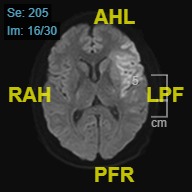

Further diagnostic workup included brain magnetic resonance imaging (MRI) and magnetic resonance (MR) angiography of intracranial vessels. The brain MRI revealed evidence of an acute infarct situated within the left middle cerebral artery (MCA) territory, affecting the left insular cortex as well as the adjacent frontal and temporal operculum (Figure 1). Additionally, the MR angiography depicted a cutoff in the M1 segment of the left MCA (Figure 2).